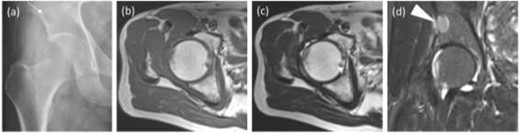

The radiographs showed calcification around the right femoral neck (Fig. 1a). The magnetic resonance image (MRI) showed an intra-articular lesion, which revealed that the mass was 40 ×10 × 42 mm and located at the anterolateral side of the femoral neck. The mass was isointense, slightly hyperintense and hyperintense compared with skeletal muscle on T1- and T2-weighted and T2 fat-saturated images, respectively (Fig. 1b–d). In addition, MRI showed a pelvic bone lesion, as well (Fig. 1d). At this point, we did not speculate the possibility of malignant tumor, then planned arthroscopic treatment for biopsy and tumor excision. A simple excision was performed via arthroscopic surgery, but the pelvic lesion was not excised. The arthroscopic image demonstrated a hyperemic soft tissue mass in the hip joint (Fig. 2). Removal of massive lesion and intra-articular debridement by shaver and radio frequency device was performed as much as possible.

Images before the arthroscopic surgery. (a) A radiograph showed the calcification at the anterolateral side of the right femoral neck (two arrows) and a radiolucent shadow of the pelvic bone (an arrow). Axial (b) T1-, (c) T2-weighted image (T1WI, T2WI) and (d) coronal T2 fat-saturated (T2 fs) image revealed the intra-articular lesion in the right hip joint (two headless arrows). The mass was 40mm×10mm×42mm and isointense, heterogenous and hyperintense to skeletal muscle on T1WI and T2WIand T2 fs images respectively. T2WI showed triple signal intensity sign9. In addition, the coronal T2 fs image showed a pelvic bone lesion (a headless arrow).